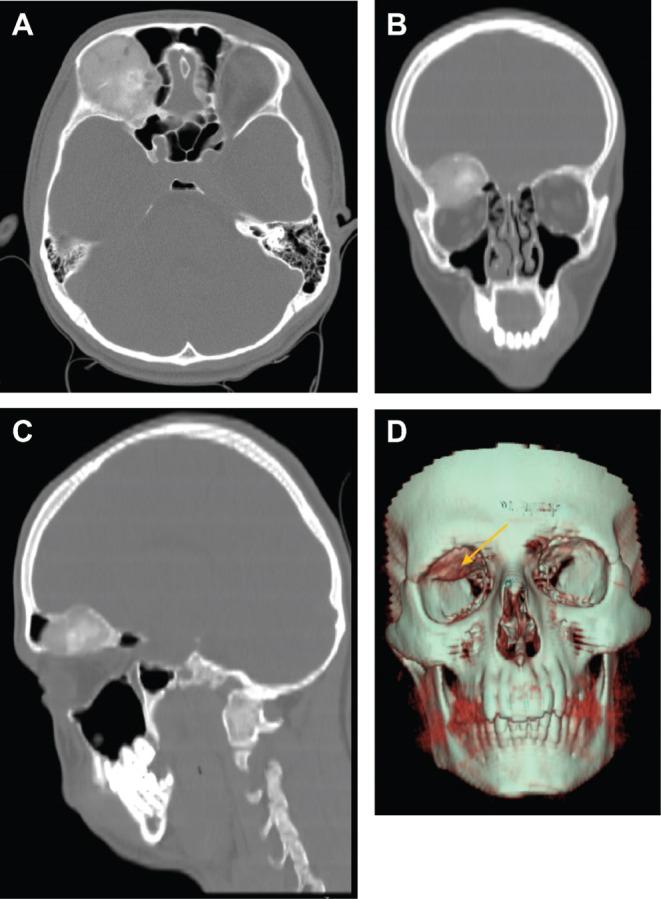

Osteoblastoma is an uncommon benign bone tumor rarely involving the craniofacial skeleton. Manifestations in the fronto-orbital region are exceptionally rare. A 19-year-old man presented with persistent headache, nausea, vomiting, right eye pain, and longstanding right exophthalmos. Imaging revealed a heterogeneous enhancing lesion located in the right anterior cranial fossa-orbital apex junction causing pressure on the orbital roof. Differential diagnoses included fibrous dysplasia and meningioma. The tumor was resected via frontal craniotomy. Definitive diagnosis of osteoblastoma was achieved postoperatively through histopathological examination and IHC studies. Craniofacial osteoblastomas, especially in the fronto-orbital region, are exceptionally rare and may present radiological features similar to other bone pathologies. Accurate diagnosis hinges on histopathological evaluation. A multidisciplinary approach is pivotal for successful diagnosis and treatment of such challenging cases.

摘要

骨母细胞瘤是一种罕见的良性骨肿瘤,很少累及颅面骨骼。额眶区域的表现极为罕见。一名19岁男性出现持续性头痛、恶心、呕吐、右眼疼痛和长期的右眼球突出。影像学检查显示一个位于右前颅窝-眶尖交界处的不均匀强化病变,对眶顶产生压迫。鉴别诊断包括骨纤维发育不良和脑膜瘤。通过额部开颅手术切除肿瘤。术后通过组织病理学检查和免疫组化研究确诊为骨母细胞瘤。颅面骨母细胞瘤,尤其是在额眶区域,极为罕见,可能呈现与其他骨病变相似的放射学特征。准确的诊断取决于组织病理学评估。多学科方法对于成功诊断和治疗此类具有挑战性的病例至关重要。